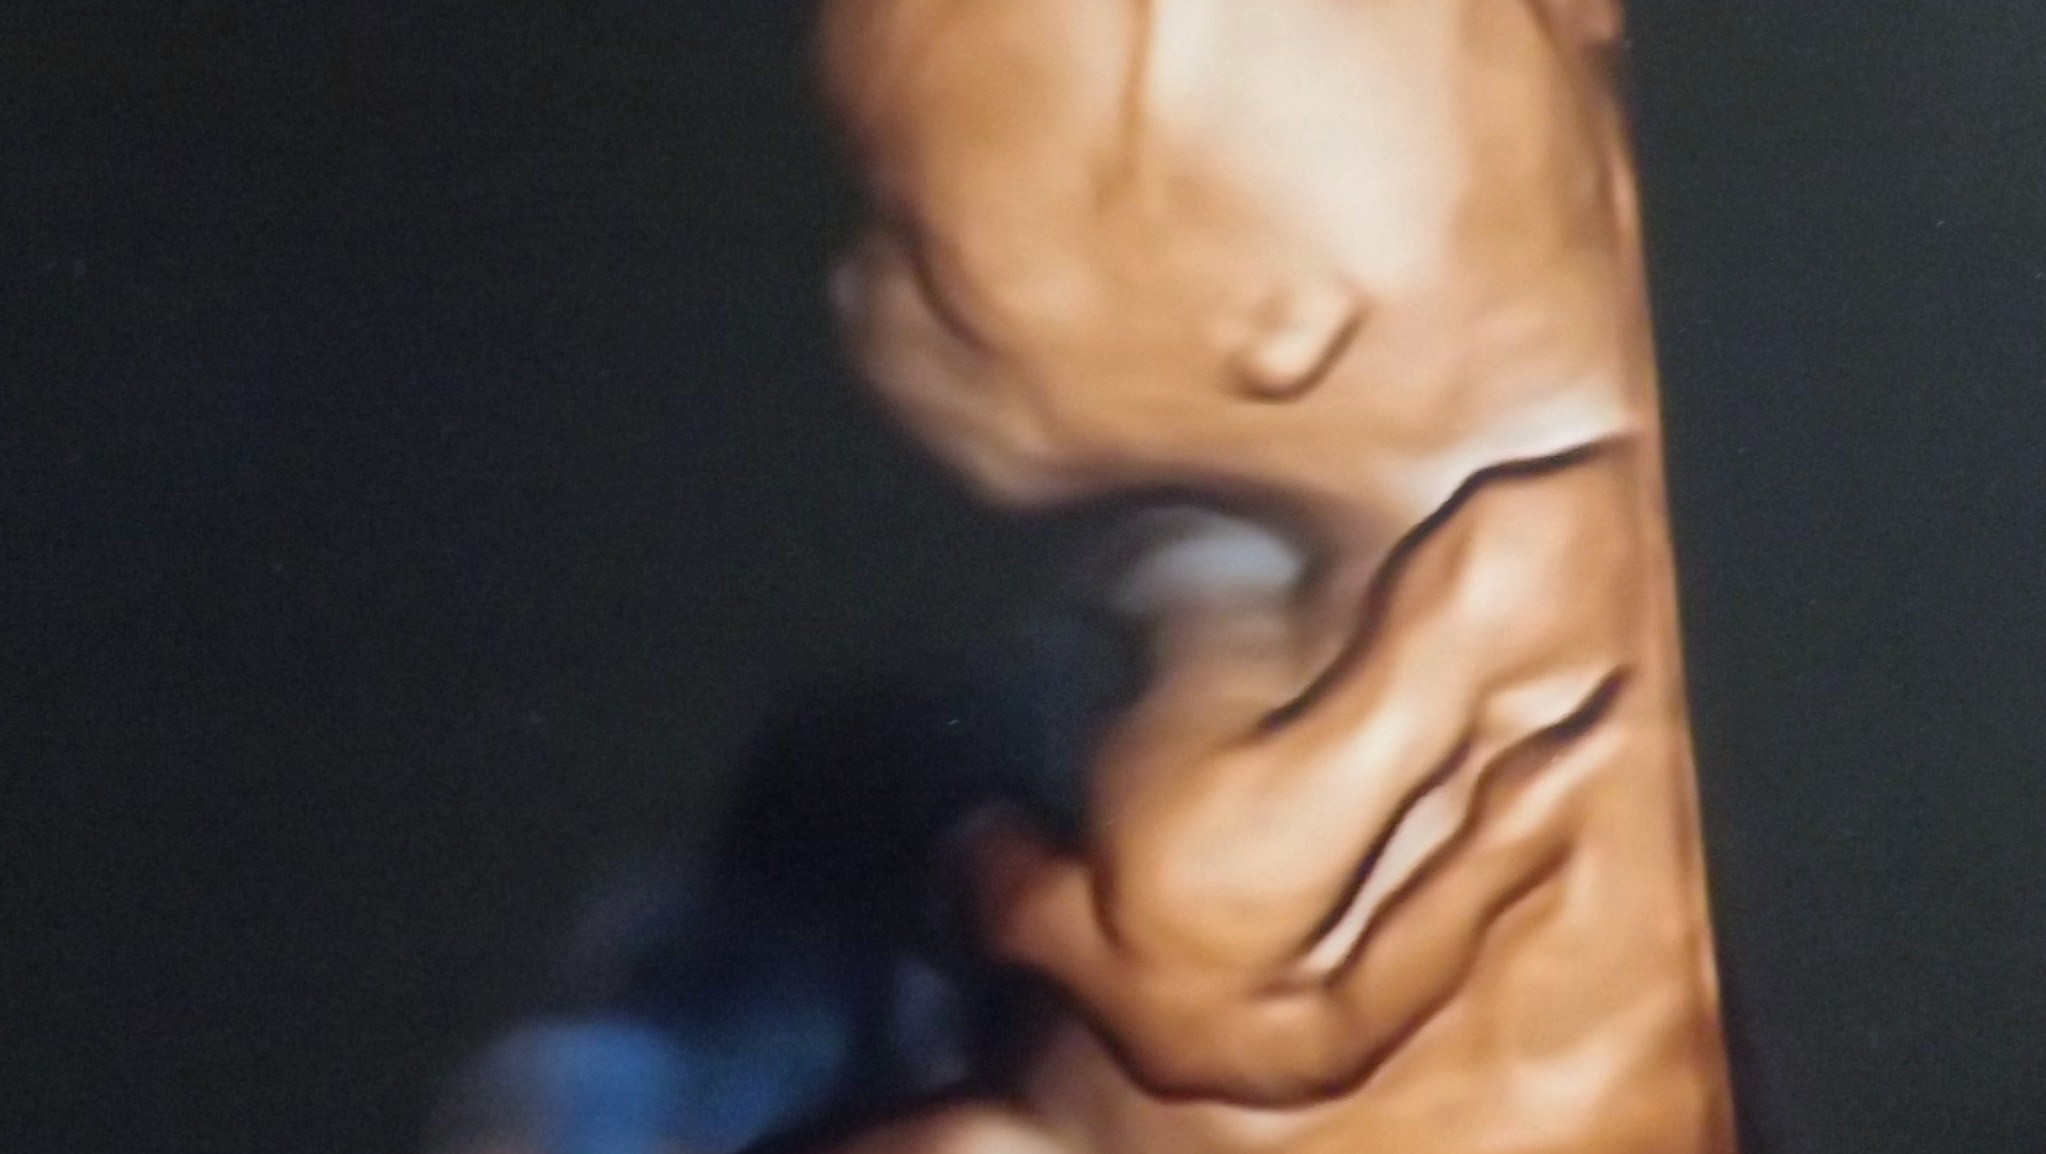

Nasze wizyty i zdjęcia USG

Wrzucam foteczkę z dzisiejszej wizyty, 12+0 i 5,28cm, rośniemy zdrowo :)